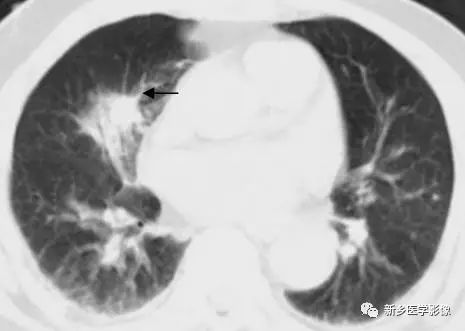

肺结核空洞CT图

a. 肺窗;b.纵隔窗,显示右上肺薄壁空洞(↑)

肺癌空洞CT图

a. 肺窗;b.纵隔窗,显示左上肺厚壁空洞(↑),内壁不规则,见壁结节

肺脓肿空洞CT图

a. 肺窗;b.纵隔窗,显示右上肺厚壁空洞(↑)周围见大片状模糊影